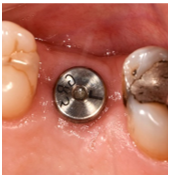

From Left to right; 1. Radiograph of placed implant with healing abutment. 2. Photograph of healed gingiva 10-weeks post-op. 3. Radiograph 1-year post-op. 4. Photograph 1-year post op of restored implant.

Patient presented 10-weeks after the implant placement, proper osseointegration was confirmed and the fixture was restored by a specialist Prosthodontist. At the 1-year supportive periodontal appointment, a diagnosis of healthy peri-implant tissues was confirmed (Figure 3 and 4).